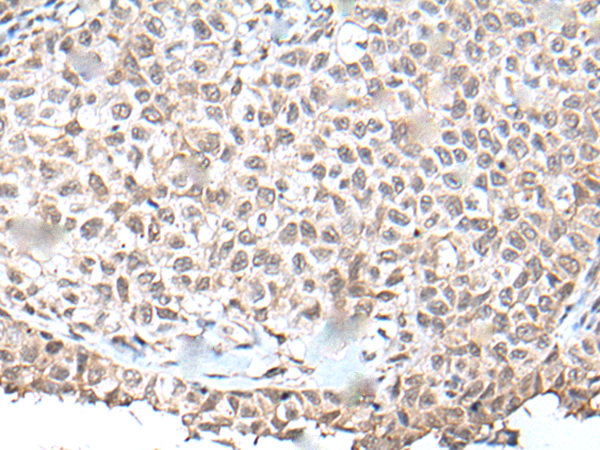

分类: 科研抗体货号: P12905别名: E4; UFD2; HDNB1; UBOX3; UFD2A应用: IHC反应种属: Human, Mouse